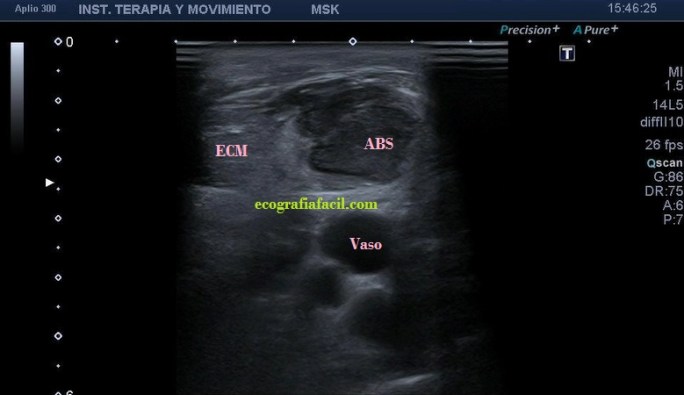

La ecografía muscular realizada evidencia una pérdida del patrón muscular normal en

el esternocleidomastoideo, con engrosamiento del mismo y semiología heterogénea en su tercio distal. Hay ganglios locorregionales hipoecogénicos con un patrón claramente reactivo aunque mantienen su tamaño subcentimétrico (Imagen 5).

A la altura de la bifurcación carotídea (imagen 6) el ECM adopta una apariencia más normal, su semiología es la típica del músculo. hipoecogénico y homogéneo, con ese patrón normal de «cielo estrellado» en eje corto como dice, mi querido amigo en sus clases, el Prof. Javier Álvarez, que tan amablemente me ha cedido estas imágenes para compartirlas en el Blog.

Desde la imagen 1 hasta la 4 realizadas en eje corto, el ECM está afectado claramente, pero en la imagen 7 donde ves un corte en eje largo puedes observar como el tejido celular subcutáneo también ha cambiado su aspecto y no es hipoecogénico, sino que es ligeramente hiperecogénico y que corresponde en cercanía con la afectación infecciosa del músculo, ojo a todos lo detalles (ganglios incluidos), que el árbol no nos impida ver el bosque…